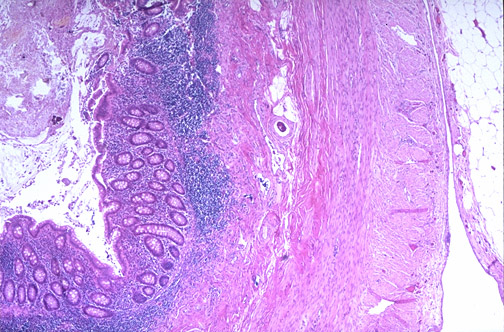

| This is the appendix at low magnification with the mucosa and the submucosa with prominent lymphoid tissue beneath which are the inner circular and the outer longitudinal smooth muscle coats, all surrounded by a serosa with adjacent adipose tissue. The lumen of the appendix is typically filled with fecal material. |